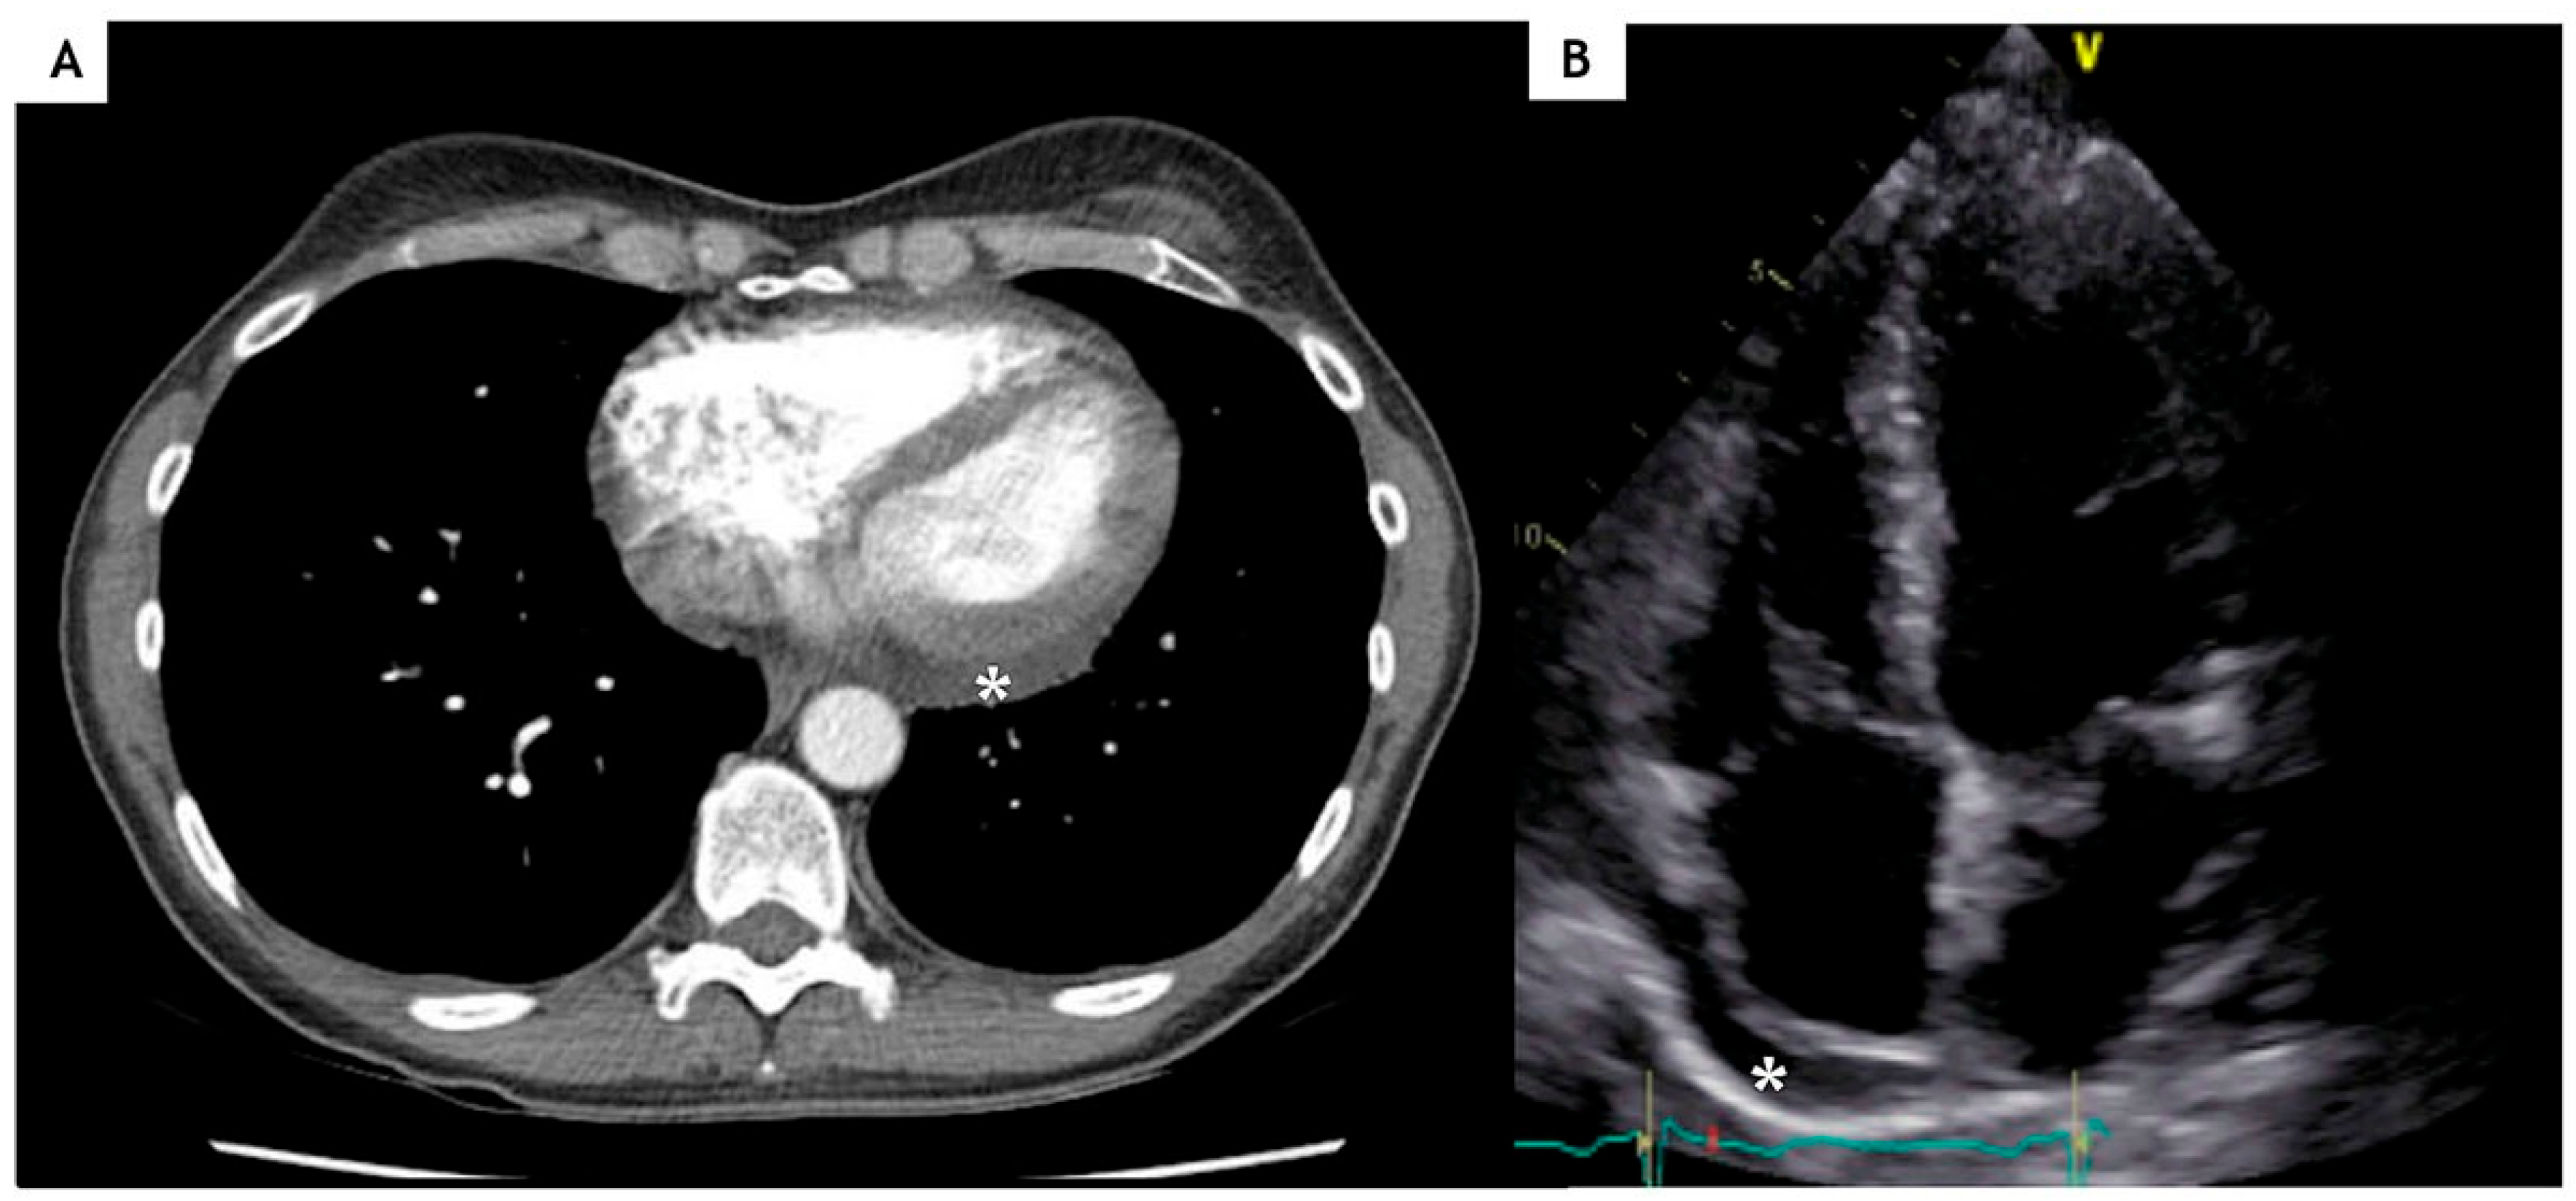

Case description